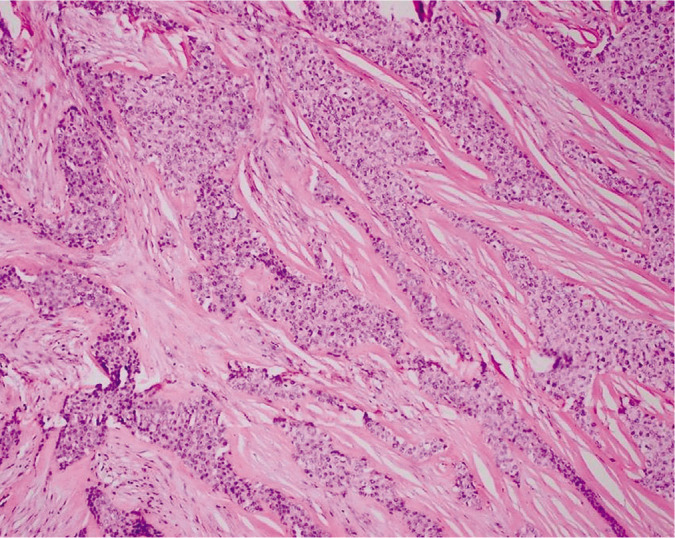

Hyalinizing clear cell carcinoma of the salivary gland is a rare neoplasm, accounting for only less than 1% of malignancies arising from the salivary gland. It is molecularly defined by the expression of the EWSR-ATF1 fusion oncogene. To date, there has been no previous studies published yet in the Philippines regarding the existence of this tumor. In this paper, we present a case of a 70-year-old elderly female who had a 10-year history of a gradually enlarging left lateral neck mass. Histopathologic examination showed a tumor arranged of cords, nests, and trabeculae of monomorphic round cells with abundant clear to lightly eosinophilic cytoplasm surrounded by thick hyalinized collagen bundles. Immunohistochemistry and molecular studies were done which revealed a positive p63 staining, negative SMA and S100, and an EWSR1 rearrangement in Fluorescence in situ hybridization (FISH), thus, confirming the diagnosis.